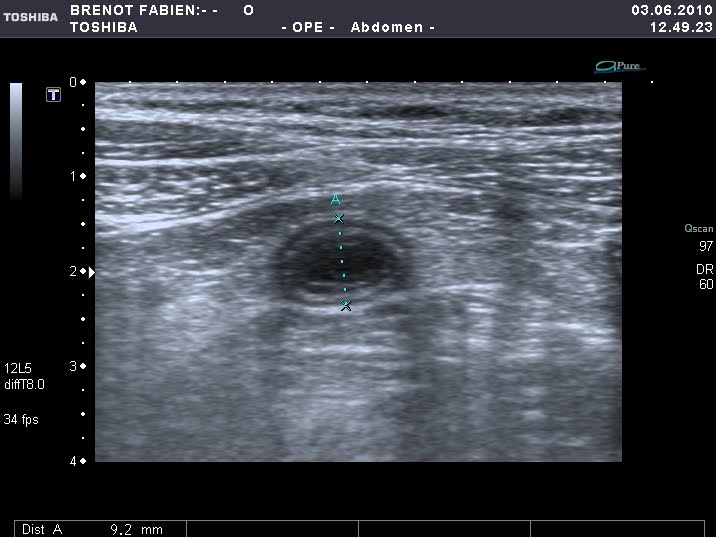

- Testes